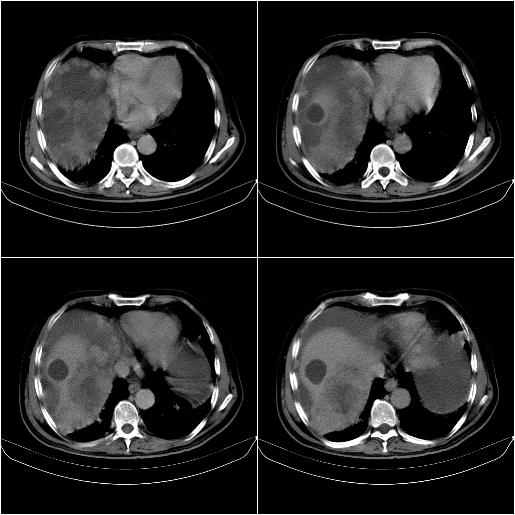

标题: CT21651:M,67Y,肝癌9月,介入术后3月。

m,67y,肝癌9月,介入术后3月。现腹胀、纳差、腹泻。

脾脏转移。。。

1)肝癌介入治疗术后碘油沉积不良。2)门静脉瘤栓形成,腹膜广泛性转移。3)肝硬化,脾大,腹水。4)慢性胆囊炎。